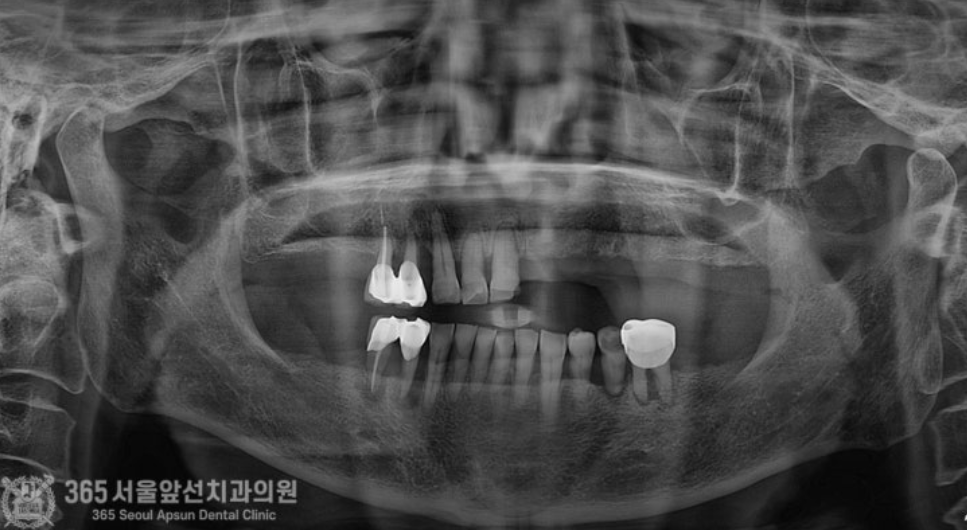

촬영일시 : 24.07.09 의식하진정법(수면치료)을 이용하여 잠자는 듯한 상태에서 수술을 진행하여 위,아래 두 번에 걸쳐 수술을 마무리 해드렸습니다. 위턱에 발치를 동반하여 7개 임플란트 식립 및 뼈이식과 양측 상악동 거상술을 포함하여 총 32분이 소요되었으며, 아래턱에 발치를 동반하여 4개 임플란트 식립 및 뼈이식에 총 15분이 소요되었습니다. 수술은 서지컬 가이드나 기타 복잡한 장비의 도움없이 진행되었습니다. 수술은 아주 잘 끝났고 환자분도 정확하고 고통없는 수술에 매우 만족하셨습니다.